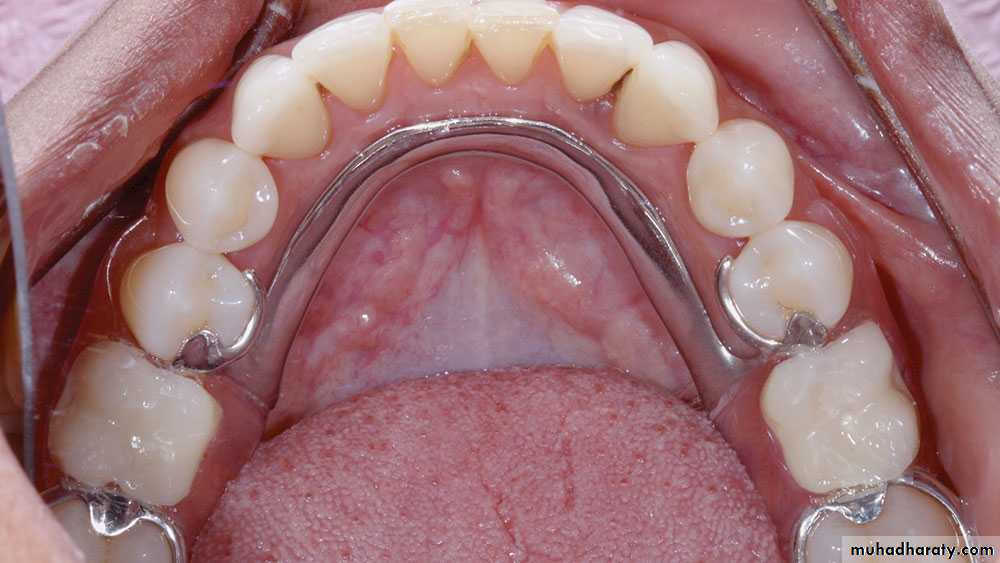

Indication of removable partial denture

1-Distal extension situations.

2-After recent extractions.

3-Long span.

4-Need for cross-arch stabilization.

5-Excessive loss of residual bone.

6-Sound abutment teeth.

7-Abutment with guarded prognosis.

8-Economic considerations.

(Phase IV) 1-Construction of removable partial denture